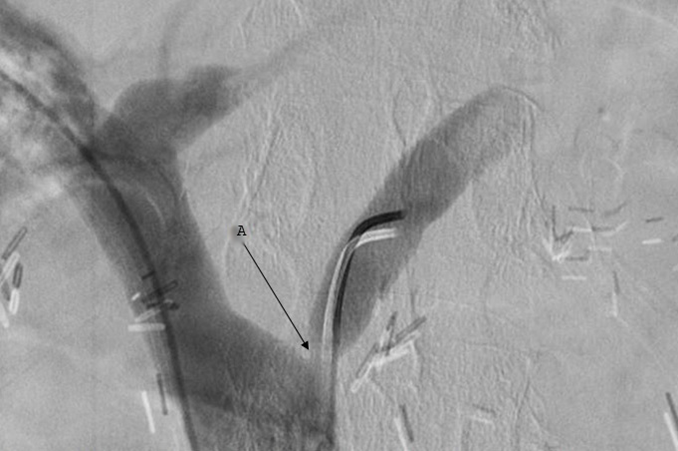

RBC scan showed a possible bleeding source in the stomach. Patient was then taken to the operating room by interventional radiology for possible embolization or TIPS. Surprisingly, there was no porto-systemic pressure gradient. Instead, patient was found to have an isolated left gastric vein stenosis (Figure 2). The stenosis was initially treated with balloon angioplasty (without significant improvement in luminal diameter or pressure gradient) and splenic artery embolization. Due to persistent melena, angioplasty was repeated resulting into 130 % luminal gain (3 to 7 mm) and a 67 % pressure gradient reduction (9 to 3 mm mercury). Despite this, patient continued to bleed and ended up having a splenectomy with eventual resolution of bleeding. Patient was then observed in the hospital for several days with repeat EGD prior to discharge revealing normal gastric mucosa with resolution of gastric varices. Prior to discharge, a thorough work up for liver disease was sent and was found to be negative (Table 1). Patient was followed up in GI clinic in the subsequent week and 2 months later and did not report any more bleeding. It was eventually concluded that patient was misdiagnosed with liver cirrhosis.

Figure 2.Venogram showing left gastric vein stenosis (A) with proximal vessel dilation.